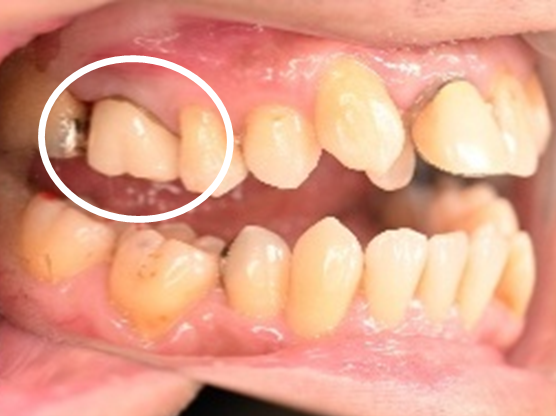

女性Sさん 50代(オールセラミック冠)

主訴

左上の差し歯がとれたままになっている。

治療内容

レントゲンを撮り詳しく診てみると、歯根が破折して保存することができず、抜歯する必要があることがわかりました。抜歯後、オールセラミックブリッジで補綴(欠損した部分を人工物で補う)しました。ブリッジの支台になっている後方の歯は、根尖性歯周炎(根の先端で問題を起こしている)でしたので、根管治療をしています。

所感

抜歯後、欠損部分を補う方法には、1本だけの部分入れ歯、ブリッジ、インプラントの3つの方法があります。この患者さんは、ブリッジを選択されました。メタルフリーの治療を希望されましたので、土台をファイバーコアにし、オールセラミックのブリッジをかぶせました。患者さんは、お口の中の金属を徐々に減らしていきたいということです。体全体の健康のことを考えると正しいことです。

オールセラミック冠(失活歯)1本:¥104,500(税込)

オールセラミック冠(生活歯)1本:¥93,500(税込)

ポンティック1本:¥93,500(税込)

合計:¥291,500(税込)

Before

After